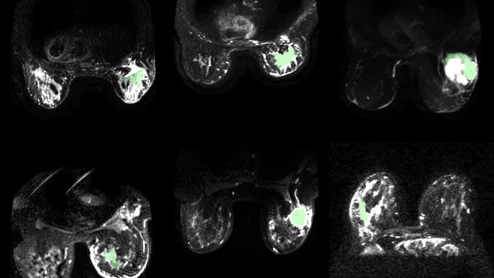

Cryoablation treatment for inoperable non-small cell lung cancer

New findings suggest that the procedure offers effective local control and a favorable safety profile for patients with medically inoperable stage 1A non-small cell lung cancer.